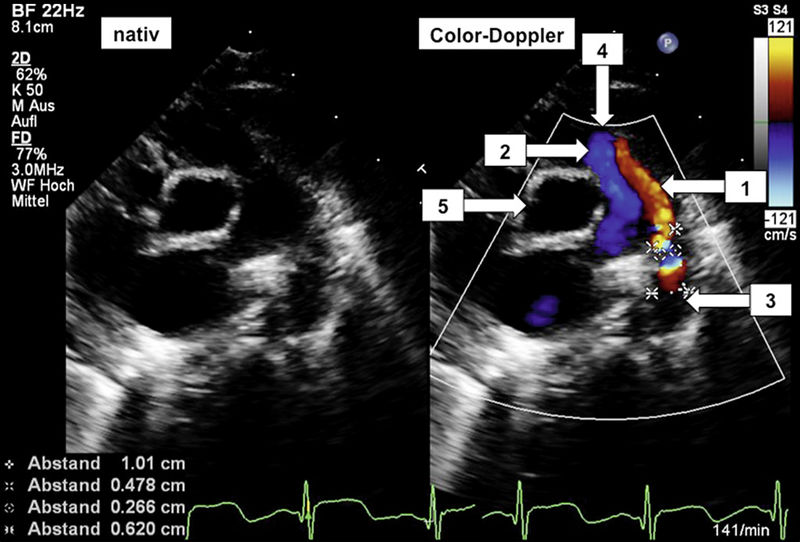

Zielsetzung der Diagnostik ist die eindeutige Darstellung der Ductus-Anatomie (Abbildung 2) sowie die Evaluation seiner hämodynamischen Auswirkungen. Das Augenmerk richtet sich dabei insbesondere auf die Shuntverhältnisse und das pulmonale Druckniveau. Die Echokardiografie hat sich seit Jahren für diese Fragestellungen als ideales diagnostisches Werkzeug etabliert und kann praktisch alle Fragestellungen zur Planung des therapeutischen Vorgehens beantworten. Gleichzeitig ist die Echokardiografie in der Lage, weitere anatomische Anomalien auszuschließen.

Abbildung 2: Echokardiografische Darstellung eines offenen Ductus Botalli, linksseitig B-Bild, auf der rechten Seite mittels Farbdoppler dargestellter Blutfluss (die mit „Kreuzchen“ markierte Strecke ist die Länge des persistierenden Ductus Botalli, der Abstand zwischen den Markierungen entspricht der relativen Breite). (1) Retrograder Ductusfluss aus der descendierenden Aorta (in Rot) zur Pulmonalklappe hin gerichtet; (2) Antegrader Blutfluss aus der Arteria pulmonalis (in Blau) in Richtung Pulmonalisbifurkation; (3) Aorta descendens; (4) Pulmonalklappenlevel; (5) Echokardiografisch quer angeschnittene Aorta ascendens.